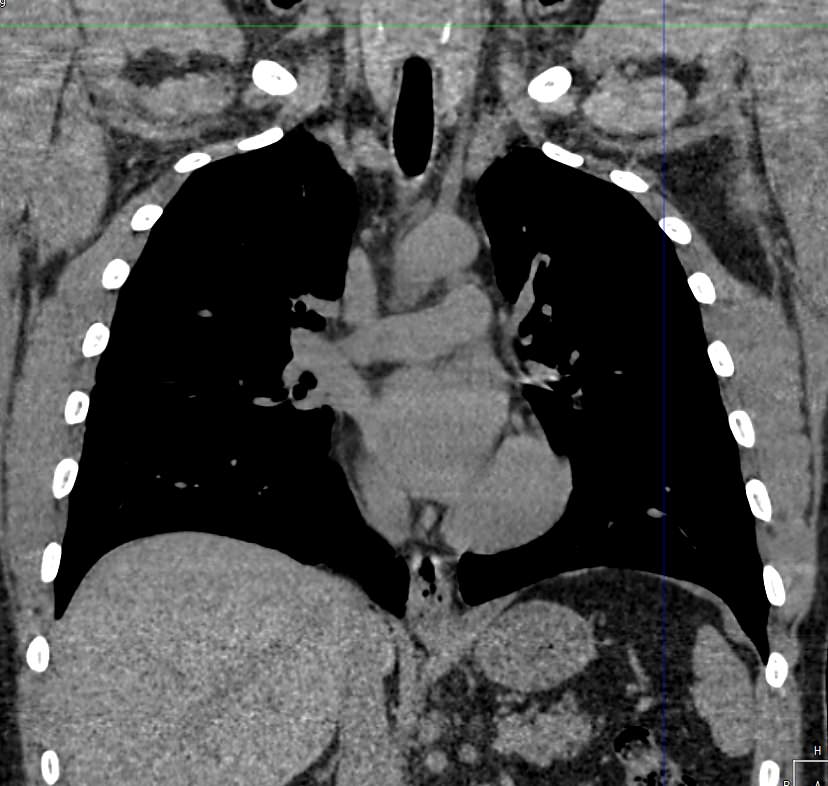

Одним из наиболее информативных методов исследования органов средостения является компьютерная томография. В основе метода лежит использование проникающего действия ионизирующего излучения для получения подробных снимков строения внутренних органов.

Инновационные технологии, которыми оснащены компьютерные томографы, послойно сканируют анатомическую область с шагом от 0,5 мм. В результате получаются снимки тонких срезов исследуемой зоны в мельчайших подробностях. С помощью цифровых приложений на основании полученных данных можно реконструировать трехмерные модели внутренних органов, что позволяет оценить структуру зоны исследования и близлежащих тканей.

Для повышения информативности компьютерной томографии (например, при подозрении на опухоли органов средостения) дополнительно назначается внутривенное болюсное контрастирование.

Для этого пациенту внутривенно вводится йодсодержащий контрастный препарат, который накапливается в патологически измененных участках и поглощает рентгеновские лучи. Такая способность рентгеноконтрастных препаратов дает возможность увидеть патологический очаг минимальных размеров на фоне здоровых тканей, что, в частности, имеет важное значение для диагностики опухолей на начальном этапе.

- Что показывает КТ органов средостения?

Что показывает КТ органов средостения?

- наличие онкологии и метастазов;

- туберкулез и другие инфекции;

- патологии диафрагмы и бронхов;

- последствия травм;

- состояние лимфоузлов;

- индивидуальные анатомические особенности;

- патологии вилочковой железы;

- новообразования из нервной ткани;

- опухоли в жировой соединительной ткани;

- патологии мышечной ткани и сосудов;

- кисты;

- эмфизему средостения;

- абсцесс, эмпиему средостения;

- аневризму аорты

- воспалительные процессы;

- болезни сосудов и тромбоэмболию.